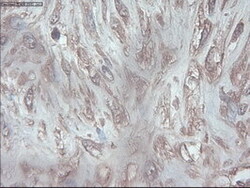

- IHC of paraffin-embedded Carcinoma of pancreas using anti-PDX1 mouse monoclonal antibody.